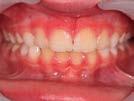

Evan Case treated with EF Class II 2 Steps

Treatment time: 12 months

Wearing of EF Class II 2 Steps for 3 months

Results: improved overhang without rabbiting

then

Wearing of EF Class II Standard for 3 months

Results: improvement in overhang, then overlay

Wearing of EF T Slim for 6 months

Results: Class II corrected • Waiting for lateral sectors (1 year after the start of treatment)